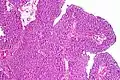

Transitional cell carcinoma, being low-grade to the left, and high-grade to the right. H&E stain

Papillary transitional cell carcinoma, low grade